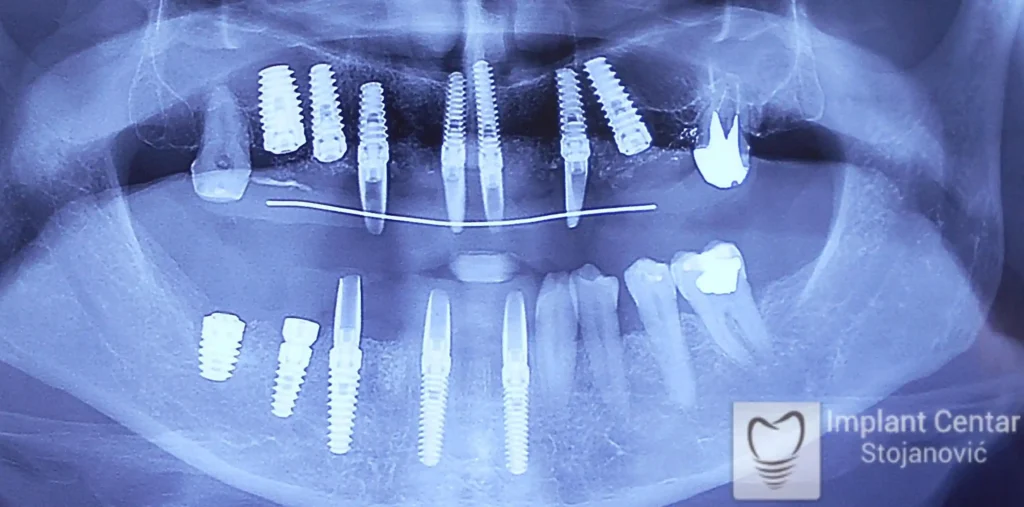

Pacijent sa rascepom usne, nepca i alveolarnog grebena uspešno je rehabilitovan fiksnim protetskim radom na implantatima. Pre dolaska u našu ordinaciju, pacijent je u gornjoj vilici nosio totalnu protezu preko preostalih zuba, dok je u donjoj vilici bio zbrinut parcijalnom mobilnom protezom. Tokom višegodišnje potrage za adekvatnim rešenjem, pacijent nije uspeo da pronađe zadovoljavajuću terapijsku opciju ni u zemlji ni u inostranstvu.

Nakon detaljnog kliničkog pregleda i analize radioloških snimaka, izrađen je sveobuhvatan plan terapije sa ciljem uklanjanja mobilnih proteza i postizanja maksimalne funkcionalne i estetske rehabilitacije. Zbog loše biološke vrednosti preostalih zuba, doneta je odluka o njihovom vađenju i ugradnji dentalnih implantata.

Poseban terapijski izazov predstavljalo je premošćavanje defekta nastalog usled rascepa, kao i ograničena količina raspoložive kosti u gornjoj vilici. Primenom većeg broja implantata i odgovarajućih procedura nadoknade kosti, postignuta je stabilna osnova za fiksni protetski rad.

Tokom perioda oseointegracije, pacijent je bio zbrinut fiksnim privremenim krunicama, čime je već pet dana nakon intervencije obezbeđena potpuna funkcionalna i estetska rehabilitacija. Nakon završetka perioda integracije implantata, izrađeni su definitivni cirkonijum-keramički mostovi na implantatima.